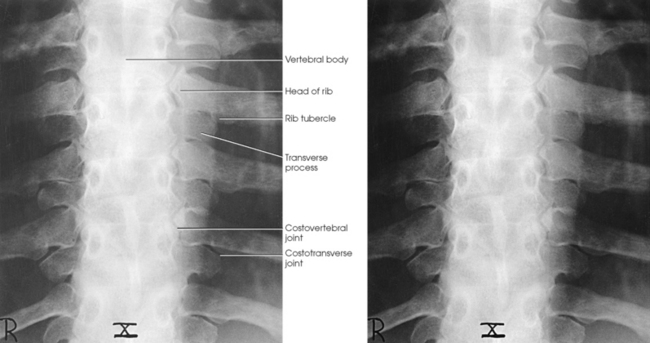

A typical rib consists of a head, a flattened neck, a tubercle, and a body (Figs. 9-5 and 9-6). The ribs have facets on their heads for articulation with the vertebrae. The facet is divided on some ribs into superior and inferior portions for articulation with demifacets on the vertebral bodies. The tubercle also contains a facet for articulation with the transverse process of the vertebra. The 11th and 12th ribs do not have a neck or tubercular facets. The two ends of a rib are termed the vertebral end and the sternal end.

Posteriorly, the head of a rib is closely bound to the demifacets of two adjacent vertebral bodies to form a synovial gliding articulation called the costovertebral joint (Fig. 9-7, A; see Fig. 9-6). The 1st, 10th, 11th, and 12th ribs each articulate with only one vertebral body.

The tubercle of a rib articulates with the anterior surface of the transverse process of the lower vertebra at the costotransverse joint, and the head of the rib articulates at the costovertebral joint. The head of the rib also articulates with the body of the same vertebra and articulates with the vertebra directly above. The costotransverse articulation is also a synovial gliding articulation. The articulations between the tubercles of the ribs and the transverse processes of the vertebrae permit only superior and inferior movements of the first six pairs. Greater freedom of movement is permitted in the succeeding four pairs.